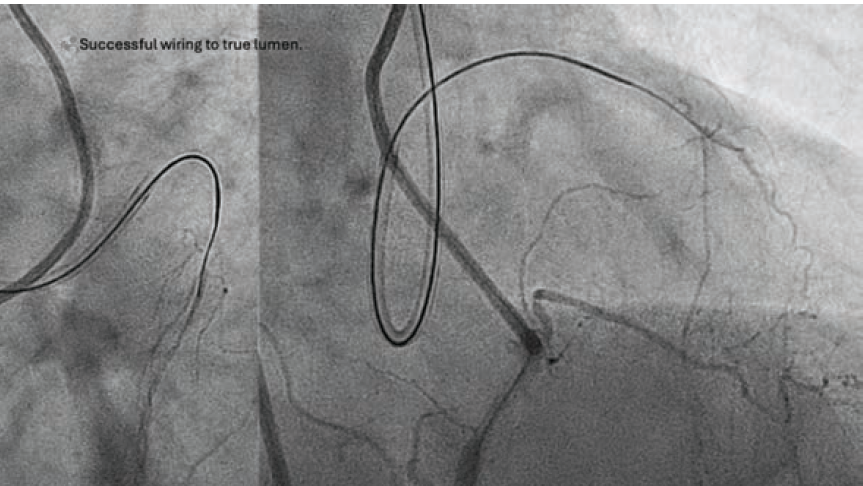

1. Ten Tips and Tricks for Successful Distal True Lumen Wiring From Three-Dimensional Wiring Experts

Wu E, Nagamatsu W, Okamura A

J Invasive Cardiol. 2024 Jun 6. doi:10.25270/jic/24.00096

Abstract: Antegrade wiring is the dominant method used in chronic total occlusion percutaneous coronary intervention (CTO PCI). However, distal cap puncture for distal true lumen wiring remains a significant barrier toward success. Three-dimensional (3D) fluoroscopic wiring can improve the speed, safety, and success of distal cap wiring. In this article, we provide 10 tips for every CTO interventionist to use when performing 3D wiring in distal true lumen wiring.